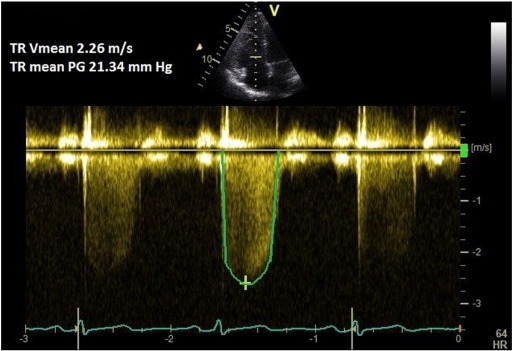

A pulmonary regurgitation (PR) signal is obtained in the parasternal short axis view using colour Doppler. CW Doppler at a sweep speed of 100 mm/s is used to measure the peak PR velocity (Fig. 3 ). Peak pressure difference (measured by the Bernoulli equation) is then added to the RAP. This method has been validated against gold standard catheter-measurements [13]  and [14] . Mean PAP can be approximated from the peak PR Doppler signal using the following formula: mPAP = 4(PRpeak velocity)2  + RAP.

Fig. 3.

Pulmonary regurgitation method for measuring mean and diastolic pulmonary artery pressure.

A PR signal is obtained as above. End PR velocity is measured in multiple (non-continuous) traces and averaged. Pulmonary artery diastolic pressure (PADP) is calculated from the following equation: 4(PR-end velocity)2  + RAP. Mean pulmonary artery pressure can be calculated from systolic (by TRmax method) and diastolic (by PR-end velocity method) pulmonary artery pressures: